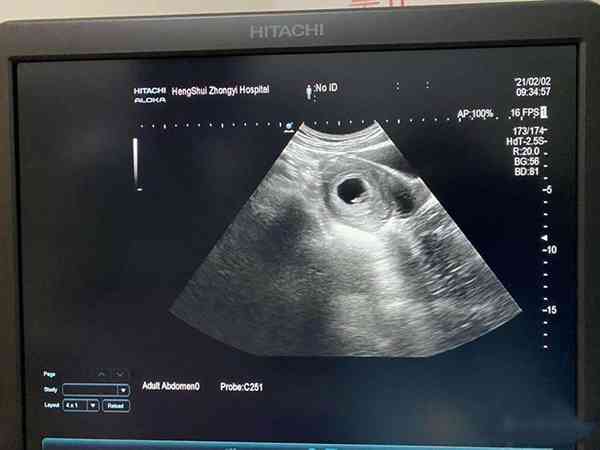

34歲頭胎懷孕,孕早期一切順利,我的雌二醇數值比較高,最近一次檢查雌二醇超過2000,在孕8周時b超檢查就已經有了胎心胎芽,我的hcg和孕酮數值也是正常的,這是不是就說明我之後就不會再面臨胎停育了?因為我聽大夫說我這個年齡懷孕很危險,要我好好保養!孕9周雌二醇超過2000有胎心胎芽表示胚胎髮育較好,但這並不代表胚胎就一定穩定了,發生胎停育的機率也是存在的。後期孕婦需要多多關注自己的hcg翻倍情況,以及孕酮數值,如果hcg翻倍不佳,同時孕酮值低於20ng/ml,那麼胎兒也是有隨時停搏的危險。只有胎盤出現後,出現胎停育的概率才會比較低,在此期間孕婦還是需要關注個人身體情況,避免危險行為。

雖然說胎停育往往發生於懷孕6-9周,在孕9周已經發現了胎心胎芽,且雌二醇數值超過了2000,那麼胎停的機率就會有所降低,但是這並不代表之後就不會再胎停,真正的穩定是需要胎盤出現。下面就為大傢俱體分析孕9周雌二醇超過2000有胎心胎芽是否還會胎停: